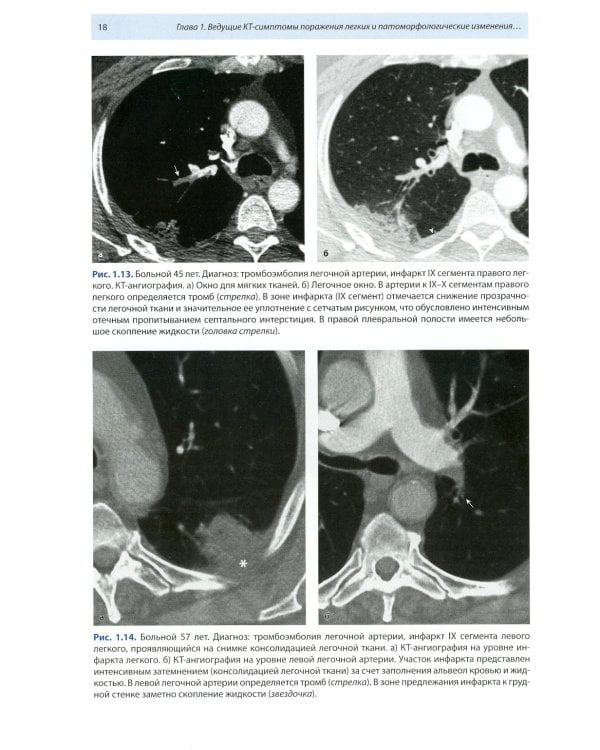

Книга составлена из двух разделов. В первом (глава 1) описаны основные симптомы патологии легких, выявляемые при КТ. Каждый из них представлен с позиции отображающих его морфологических изменений. В краткой форме описаны заболевания, проявляющиеся конкретным симптомом. Второй раздел книги состоит из трех глав, в которых отражены современные взгляды на наиболее часто встречающуюся патологию легких (пневмония, туберкулез, рак) и показаны возможности КТ в выявлении этих заболеваний. Издание предназначено для врачей лучевой диагностики, терапевтов, интернов и студентов старших курсов, интересующихся проблемами рентгенологии.| Издательство | МЕДпресс-информ |